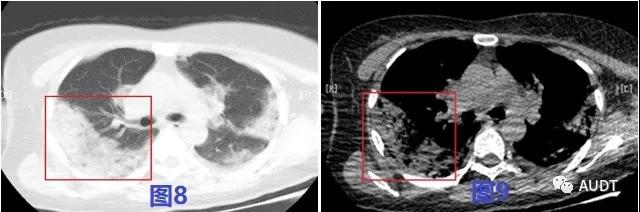

进展后期,图8-9 CT扫描显示双肺呈大片样,条带样实变影,图10-12超声显示相应肺周胸膜局限性增厚。实变病灶内超声可见粗大支气管充气征,伴病灶后弥漫性B线,实变区域实变与正常肺组织交界区可见少量星点状血流信号。